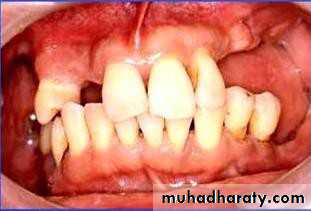

• 1) Few remaining teeth or teeth with an unfavourable distribution in the arch which precludes treatment with a removable P.D.

• 2) Severe loss of periodontal attachment in a patient who cannot afford a fixed partial denture

• 3) Complicated functional and aesthetic conditions due to tooth migration which make restoration with a removable or fixed partial denture difficult.

• 4) Significant tooth loss due to attrition.

• 5) Congenital absence of teeth i.e. Partial anodontia.